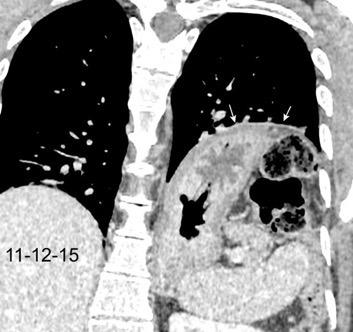

T. mixto de células germinales del testículo izquierdo

Nódulos pulmonares múltiples. (flechas verdes). Masas paratraqueales. (flechas amarillas). Dudoso ensanchamiento retrocrural (flechas negras). sigue….

Ttawfik A et al. Trans-diaphragmatic Pathologies: Anatomical Background and Spread of Disease on cross-sectional Imaging. Current Problems in Diagnostic Radiology. 2021.

T. mixto de células germinales del testículo

izquierdo Metástasis pulmonares. (flechas verdes). Ganglios paratraqueales. (flechas amarillas). Ganglios retroperitoneales (flechas negras)

Tawfik A et al. Trans-diaphragmatic Pathologies: Anatomical Background and Spread of Disease on cross-sectional Imaging. Current Problems in Diagnostic Radiology. 2021.